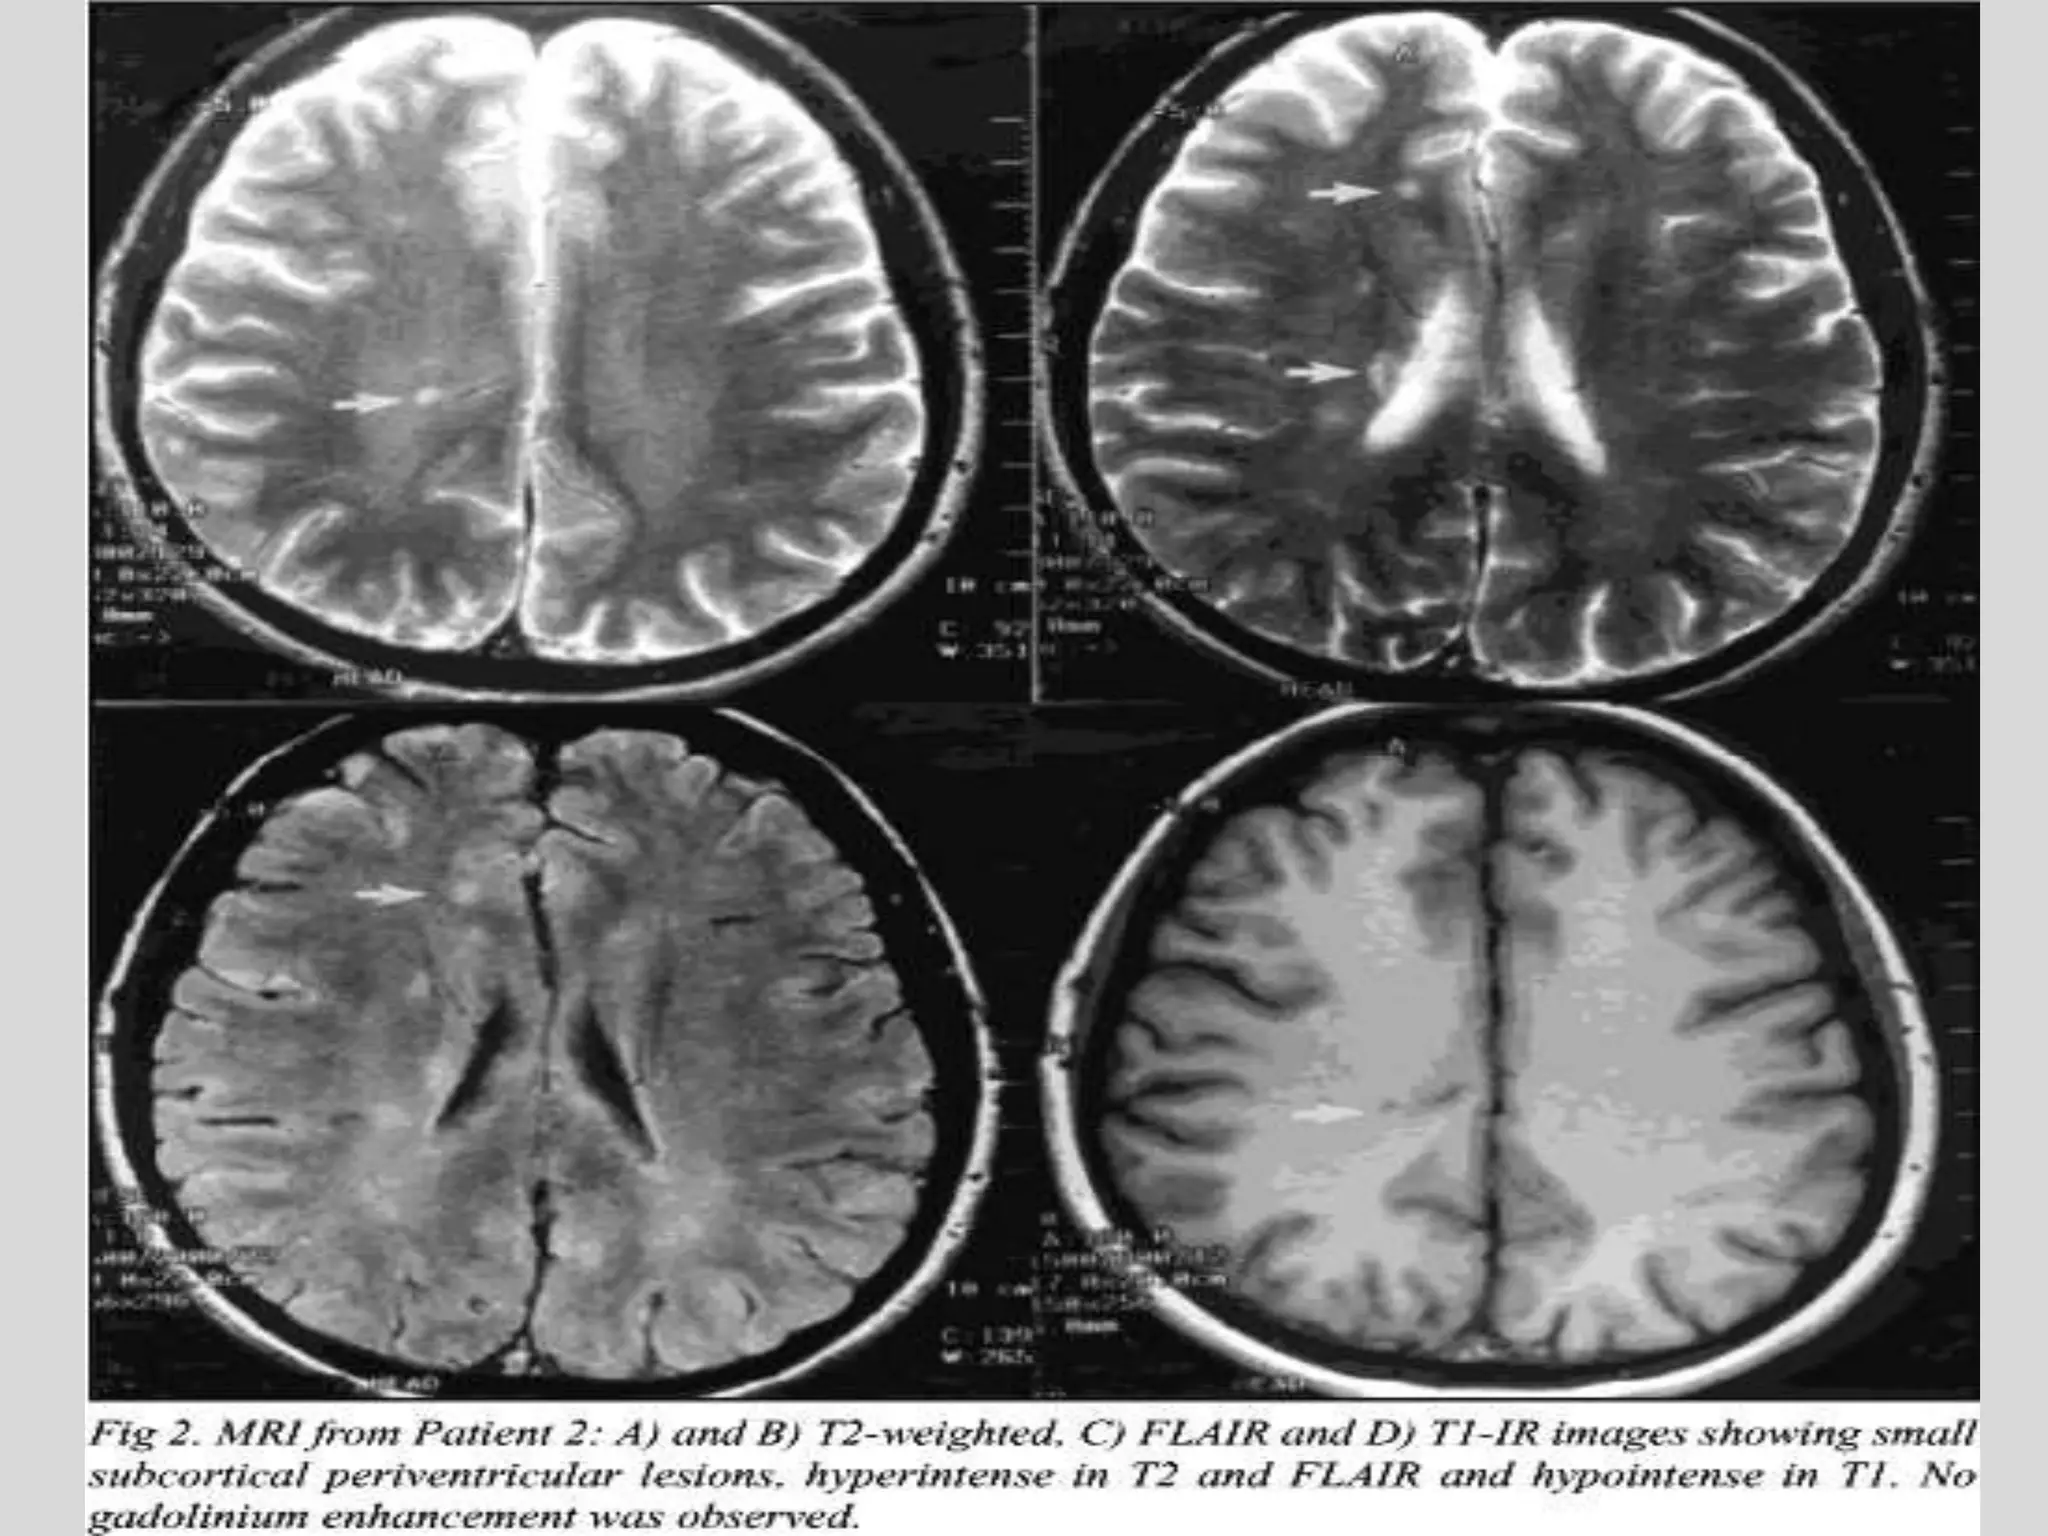

DEMYLINATING DISORDERS

MS-axial T2-weighted image. Plaques are mainly

periventricular, oval shaped with a major transverse axis,

hyperintense with respect to normal parenchyma

RING ENHANCEMENT FOLLOWINF GADOLLIUM INJECTION

DEMYLINATING DISORDERS MS-axialT2-weighted image. Plaques are mainly periventricular, oval shaped with a major transverse axis, hyperintense with respect to normal parenchyma RING ENHANCEMENT FOLLOWINF GADOLLIUM INJECTION